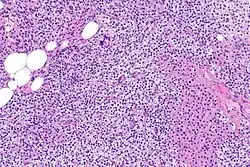

La hiperplasia primaria de la glándula paratiroides se debe tanto a la hipocalcemia como al aumento de los niveles de fosfato al disminuir la expresión de los receptores de vitamina D en la glándula paratiroidea.[8][4] Esta disminución en la expresión de receptores conduce a un hiperfuncionamiento de la paratiroides. Se cree que la hiperfunción de la glándula paratiroidea exacerba la hiperplasia primaria que evoluciona a una hiperplasia secundaria más agresiva. Histológicamente, estas glándulas pueden ser difusas o nodulares.[24] La hiperplasia primaria, que por lo general se trata de un crecimiento policlonal difuso, está relacionada con el hiperparatiroidismo secundario reversible. La hiperplasia secundaria de la glándula paratiroides es más a menudo un crecimiento monoclonal nodular que sostiene el hiperparatiroidismo secundario y es el catalizador en la progresión al hiperparatiroidismo terciario. Las glándulas hiperplásicas nodulares en el hiperparatiroidismo terciario son claramente más grandes tanto en tamaño absoluto como en peso. Se han informado de aumentos de 20 hasta 40 veces.[25][26]

Las glándulas paratiroides están normalmente compuestas de células principales, adipocitos y células oxifílicas esparcidas.[27][14] Se piensa que las células principales son las responsables de la producción, almacenamiento y secreción de hormona paratiroides. Estas células aparecen claras y oscuras con un aparato de Golgi prominente y retículo endoplásmico. En micrografías con microscopio electrónico, las vesículas secretoras se pueden ver dentro y alrededor del aparato de Golgi y en la membrana celular. Estas células también contienen grasa citoplásmica prominente. Al inicio de la hiperplasia, estas células están descritas formando un patrón nodular con aumento de la maquinaria de síntesis de proteínas como el retículo endoplásmico y el aparato de Golgi. También se aumenta el número de vesículas secretoras que puede ser vistas y disminuye la grasa intercelular.[24] Las células oxifílicas también parecen hiperplásicas, sin embargo, estas células son mucho menos prominentes.